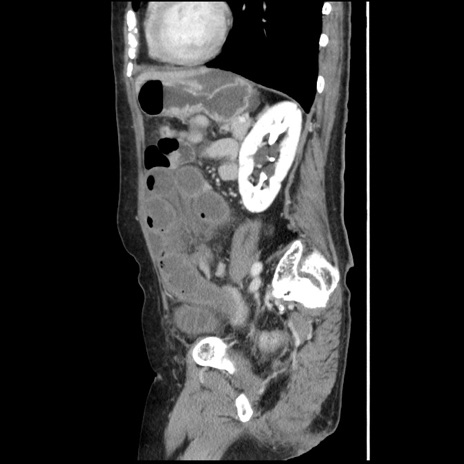

横断像

【症例】80歳代女性

【主訴】腹痛

【現病歴】8時間前から腹痛あり来院。

【既往歴】糖尿病、脂質異常症、子宮体癌にて子宮全摘術

【身体所見】意識清明・会話良好だが腹痛で苦悶様、全腹部にわたって反跳痛と圧痛あり

【データ】WBC 13600、CRP 0.14、LDH 224、CK 90